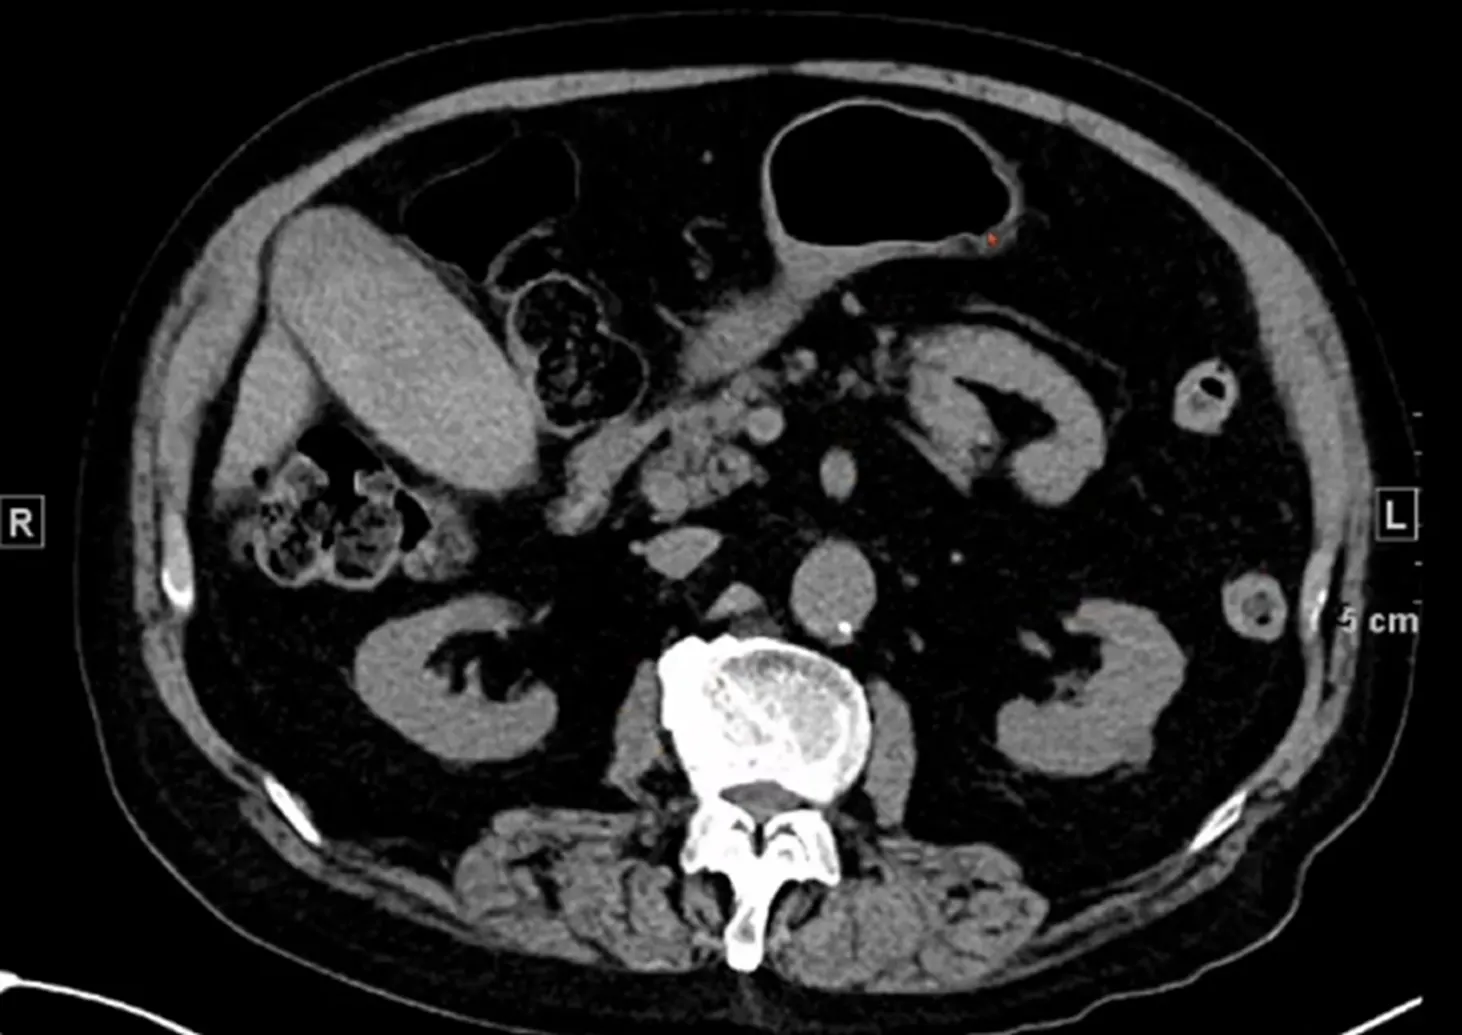

Case 10-2

•

M/43

C/C: Abdominal pain, aggravation

Hx : h/o ureter stone

Lab: within normal limit